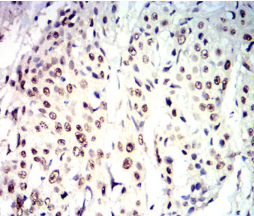

CDX2 Mouse Monoclonal antibody[5B4C1]

IHC    1/200-1/1000